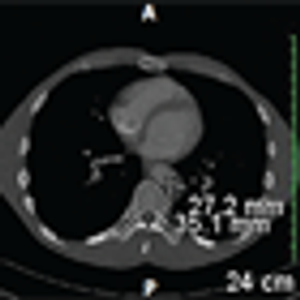

A 47-year-old woman with a history of drug-resistant epilepsy during childhood presented to the emergency department with sudden dyspnea and chest pain. Upon admission, her oxygen saturation was 88%.